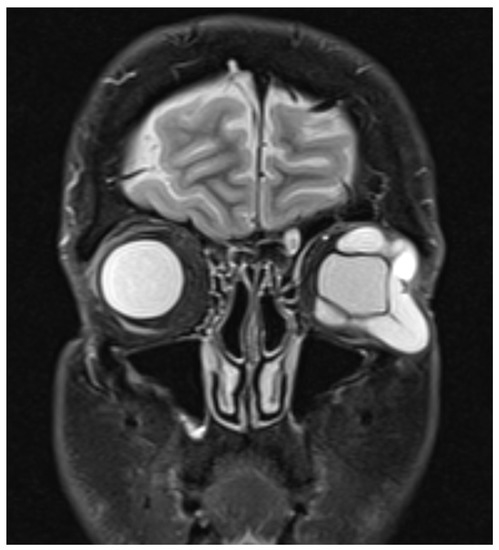

2. Case Report